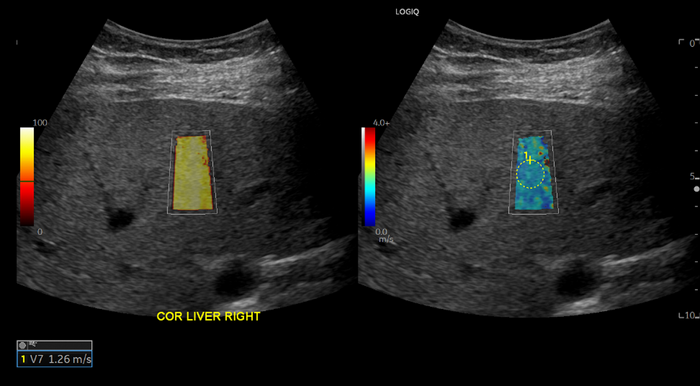

In the retrospective study, the researchers compared liver stiffness of patients with a history of COVID-19 infection to two control groups. All patients underwent ultrasound shear wave elastography between 2019 and 2022 at Massachusetts General Hospital. Shear wave elastography is a specialized technique that uses sound waves to measure the stiffness of tissue.

The patients were categorized into one of three groups based on when they underwent elastography and whether they tested positive for COVID-19. The COVID-19 positive group contained 31 patients who had a positive COVID-19 PCR test result at least 12 weeks before the elastography exam. The pandemic control group consisted of a random sample of 50 patients who underwent elastography during the COVID-19 pandemic and had a history of only negative COVID-19 PCR test results. The pre-pandemic control group consisted of a random sample of 50 patients who underwent an elastography exam prior to the COVID-19 pandemic.

After controlling for age, sex and time period, a statistical analysis of the elastography results revealed that COVID-positive patients had a statistically significant higher liver stiffness than the control patients.

COVID-positive patients had a higher median live stiffness (7.68 kPa) than pandemic control patients (5.99 kPa).

Unexpectedly, the pre-pandemic control group also had a higher median stiffness (7.01) compared to pandemic control group. The reason for this finding is not yet understood but is believed to be a result of changing referral patterns during the pandemic. Additionally, patients referred for elastography before the pandemic were noted to be older than patients referred after the start of the pandemic.